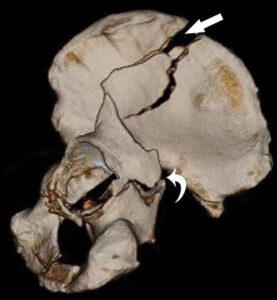

حالات سريرية:

خلال الفترة الماضية، تعاملت مع حالتين من أكثر الحالات تحديًا في جراحة العظام …………….. اقرأ المزيد